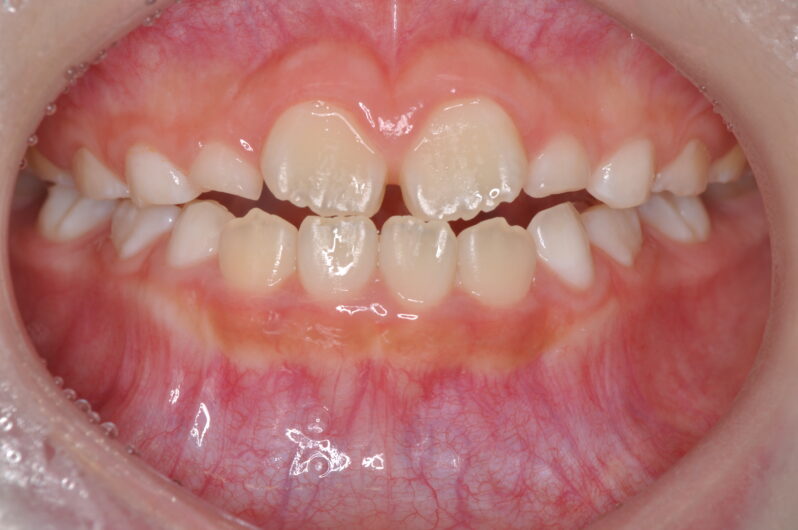

治療の途中経過

経過写真を見ると、数カ月で劇的に前歯のかみ合わせが変化しています。顎外装置を使わずとも、正確な診断と成長誘導を踏まえた治療方針があれば、ここまで自然に改善できます。